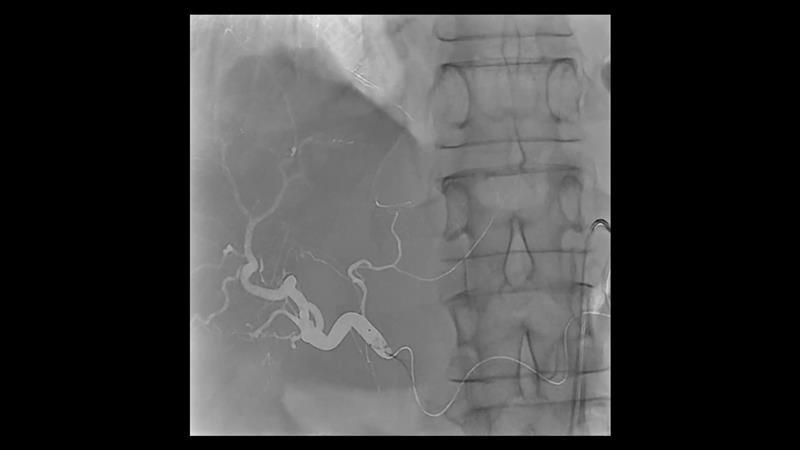

During minimally invasive procedures, it is critical to have a clear view of anatomies and devices. Yet complex imaging tasks or challenging patient conditions often impact image quality. OPTIQ AI delivers constant image quality1 defined by CNR in support of the ALARA principle, independent of patient or C-arm angulation. On top, an AI-powered algorithm reduces image noise in real time across different 2D imaging modes.

Make AI-powered imaging and clear insights your standard during interventions – with OPTIQ AI.

Future-focused IR imaging for a broad procedure mix

Discover how leading clinicians are transforming interventional radiology with Siemens Healthineers technologies. From ultra-fast 3D imaging to laser-guided needle procedures, the ARTIS icono ceiling powered by OPTIQ and syngo DynaCT are redefining what’s possible in IR. Explore real-world cases, expert insights, and the future of image-guided therapy.